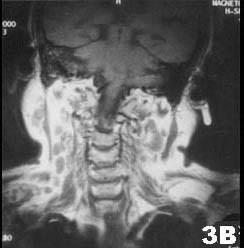

肺结核患者发现双侧腮腺区肿块3个月,缓慢增大,无明显症状。查体腮腺区可触及局限性肿块,边界清,质软,可活动,轻压痛。CT 检查结果图示。首先考虑的诊断为 ...

问题 肺结核患者发现双侧腮腺区肿块3个月,缓慢增大,无明显症状。查体腮腺区可触及局限性肿块,边界清,质软,可活动,轻压痛。CT 检查结果图示。首先考虑的诊断为 ( )

选项 A.腮腺囊肿 B.腮腺结核 C.慢性腮腺炎 D.腮腺腺样囊性癌 E.腮腺多形性腺瘤

答案 B